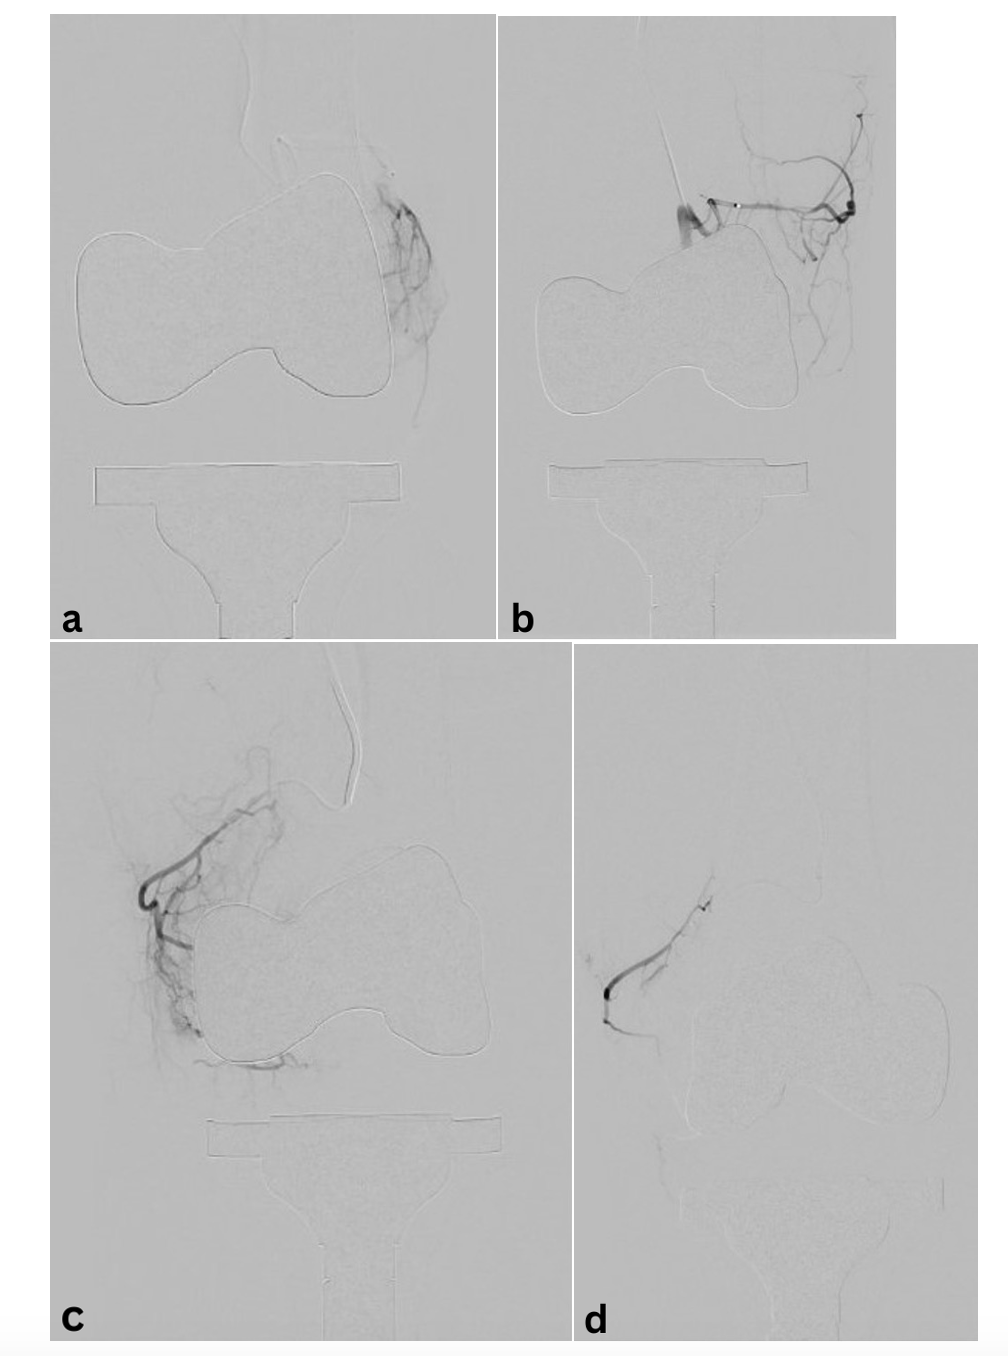

Oblique imaging may be necessary to identify the origin of the genicular arteries, particularly in the postoperative setting. Angiography will aid in identifying areas of synovial blush with the joint space. This finding is largely thought to be representative of synovial hyperemia secondary to angiogenesis. The 5F base catheter should be advanced as close as possible to the ostium of the desired genicular branch for stability as the microcatheter system is deployed. Standard microcatheter systems (2.4F to 2.8F) may not be successful for smaller tortuous vessels, and a smaller system may need to be utilized. For hemarthrosis, embolization is performed using particles ranging from 300 to 500 µm.13 In the setting of GAE treatment for OA, studies have been performed using much smaller particles, typically ranging from 100 to 300 µm. Larger embolic particles may be associated with reduced nontargeted embolization, such as cutaneous branches and those supplying ligamentous components of the joint.14 The endpoint of embolization is pruning of the neovascularity with preservation of the normal genicular artery.

See Figure 1 and Figure 2 for cases of knee OA treated with GAE.